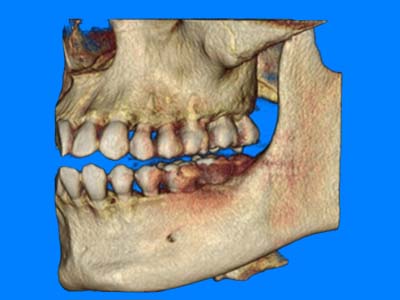

Proactive Dental Management thru our 3D Imaging Manipulation Software

With Oral Maxillofacial CT Scans, your dentist enhances his ability to proactively manage your health concern thru accurate diagnosis & better treatment planning. Moreover, the patient benefits from a painless,low radiation dose CT Scan procedure.